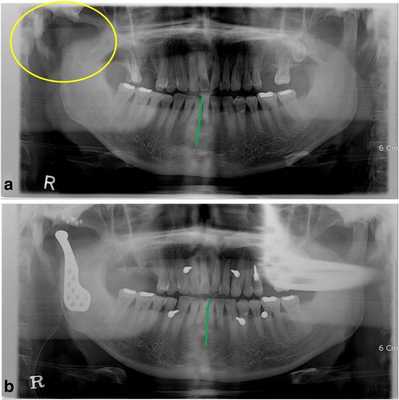

52-летний мужчина обратился за помощью по причине нарушения прикуса после кондилэктомии. Он упал вниз по лестнице и сломал нижнюю челюсть в области шейки суставного отростка. В больнице ему провели открытую редукцию поврежденной области с фиксацией частей сустава. После операции произошло инфицирование области правого ВНЧС, из-за чего пришлось провести удаление суставного отростка. Через месяц после оперативного вмешательства он обратился за помощью в стоматологическую клинику Университета Йонсей. В состояние покоя его нижняя челюсть была смещена вправо, а окклюзионное соотношение челюстей было нарушено вследствие кондилэктомии (фото 1а).

Фото 1.

а) Смещение нижней челюсти вправо (зеленая линия) в результате кондилэктомии (желтый круг).

b) Панорамная рентгенограмма, полученная через 1 день после операции, продемонстрировала восстановление окклюзионного соотношения (зеленая линия). Для стабилизации окклюзии во время операции были использованы межчелюстные фиксационные винты.

Диапазон раскрытия рта был ограничен расстоянием в 30 мм. После назначения пероральных антибиотиков с целью обеспечения инфекционного контроля была запланирована операция по реконструкции правого ВНЧС с использованием суставного протеза. Во время операции хирурги обеспечивали стабилизацию окклюзии путем межчелюстной фиксации для восстановления первоначального соотношения верхней и нижней челюстей. Установку суставного протеза проводили через два разреза: один – в околоушной области, другой – в подчелюстной по Risdon. Панорамная рентгенограмма, полученная через день после операции, подтвердила восстановление нормального окклюзионного соотношения (фото 1b). Через 3 дня пациента выписали без каких-либо осложнений послеоперационных осложнений, обеспечивая наблюдение на протяжении одного года. Протез функционировал достаточно хорошо, а восстановленная окклюзия оставалась стабильной, хотя максимальное открытие полости рта так и не удалось увеличить более чем до 30 мм.